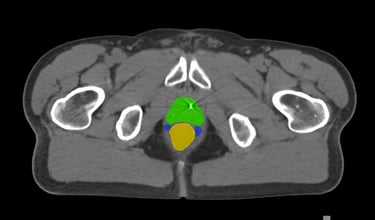

The DAM Contour features a comprehensive collection of OARs and CTVs that are ready for immediate use, without the need for manual creation of atlases or manual adjustment of data. This product includes all standard OAR and CTV structures (over 117 in total).

The Pelvis lymph node region encompasses lymph nodes that include the obturator lymph nodes, internal and external iliac lymph nodes (limited anteriorly at the level of the femoral heads), and extends up to the common iliac lymph nodes, covering the L5/S1 region.

Pelvis